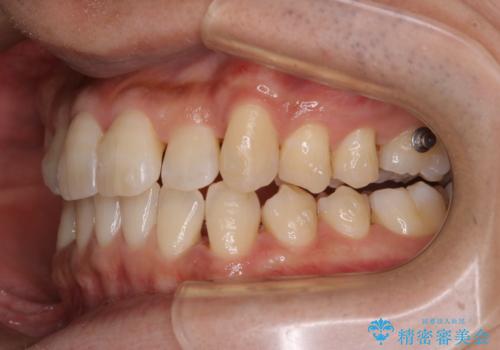

マウスピース矯正インビザライン治療では、歯の表面にアタッチメントという突起を設定します。(アタッチメントは歯の動きを効率的に移動するためのものです)

アタッチメントが歯に付くと、表面が凸凹し磨き残しが多くなったりと、プラークや歯石・着色がつきやすくなることがあります。

矯正治療中もPMTCを定期的に行い、専門的な機械でしっかりと汚れを除去することがおススメです。